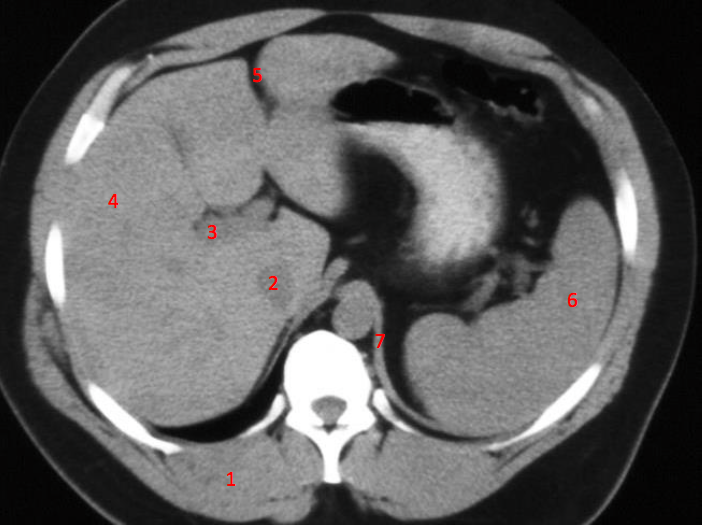

Number 3?

IVC

Number 2?

Gall bladder

Number 7?

Unlabeled

Bowel (probably large)

Number 6?

Stomach